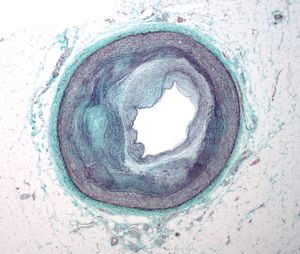

동맥은 일반적으로 현미경으로 연구되지는 않지만, 다음 두 가지 플라크 유형을 구별할 수 있다.[70]

- 섬유지질 플라크는 동맥의 내막 아래에 지질이 풍부한 세포가 축적되는 특징이 있다. 일반적으로 동맥벽의 경계 근육층이 보상적으로 확대되어 내강이 좁아지지는 않는다. 내피 아래에는 플라크의 죽상"핵"을 덮는 "섬유 캡"이 있다. 핵은 지질이 풍부한 세포(대식세포 및 평활근 세포)로 구성되어 있으며 조직 콜레스테롤과 콜레스테롤 에스터 함량, 피브린, 프로테오글리칸, 콜라겐, 엘라스틴, 세포 잔해가 증가한다. 진행된 플라크에서는 플라크의 중앙 핵에 일반적으로 세포 외 콜레스테롤 침착물(사멸한 세포에서 방출됨)이 포함되어 빈 바늘 모양의 틈이 있는 콜레스테롤 결정 영역이 형성된다. 플라크의 주변에는 더 젊은 "거품" 세포와 모세 혈관이 있다. 이러한 플라크는 파열될 때 일반적으로 개체에게 가장 큰 피해를 준다. 콜레스테롤 결정도 역할을 할 수 있다.[71]

- 섬유 플라크는 내막 아래, 동맥벽 내에 국한되어 벽의 비후 및 확장을 유발하며, 때로는 근육층의 위축과 함께 국소적인 내강 협착을 유발한다. 섬유 플라크에는 콜라겐 섬유(호산성), 칼슘 침전물(헤마톡실린성), 드물게 지질이 풍부한 세포가 포함되어 있다.

동맥벽의 근육 부분은 존재하는 죽상종을 담을 수 있을 정도로 충분히 큰 작은 동맥류를 형성한다. 동맥벽의 근육 부분은 죽상 플라크를 보상하기 위해 재형성된 후에도 일반적으로 강하게 유지된다.

그러나 혈관벽 내의 죽상종은 부드럽고 탄성이 거의 없어 부서지기 쉽다. 동맥은 각 심장 박동, 즉 맥박에 따라 끊임없이 팽창하고 수축한다. 또한, 죽상종의 외부 부분과 근육벽 사이에 진행되면서 칼슘 침착이 발생하면 전체 동맥의 탄성이 손실되고 뻣뻣해진다.